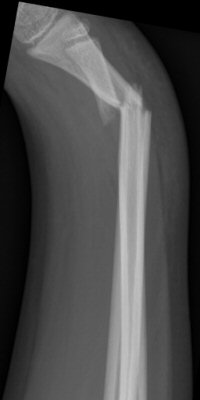

Monteggiafraktur: fraktur på ulna och samtidig luxation av caput radii. Man är inte helt överens om ulnafrakturen ska vara i den proximala tredjedelen [2] eller proximala två tredjedelarna av ulna [3]. Radiushuvudet kan också vara frakturerat istället för luxerat [2].

Monteggiafraktur, opererad med TEN-spik